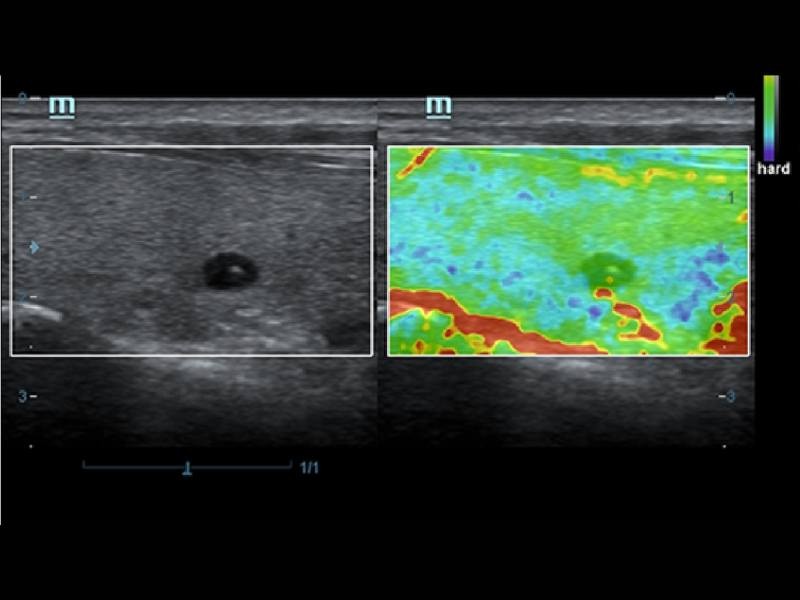

Comparados aos transdutores tradicionais, os transdutores ComboWave utilizam um novo tipo de material piezoelétrico composto a fim de otimizar drasticamente o espectro acústico e reduzir a impedância acústica. Melhor integrados à exclusiva tecnologia 3T da Mindray, os transdutores lineares ComboWave permitem desfrutar de um desempenho excepcional proporcionado por incríveis resoluções e consistência das imagens em tireoide, mama, vascular e mais.